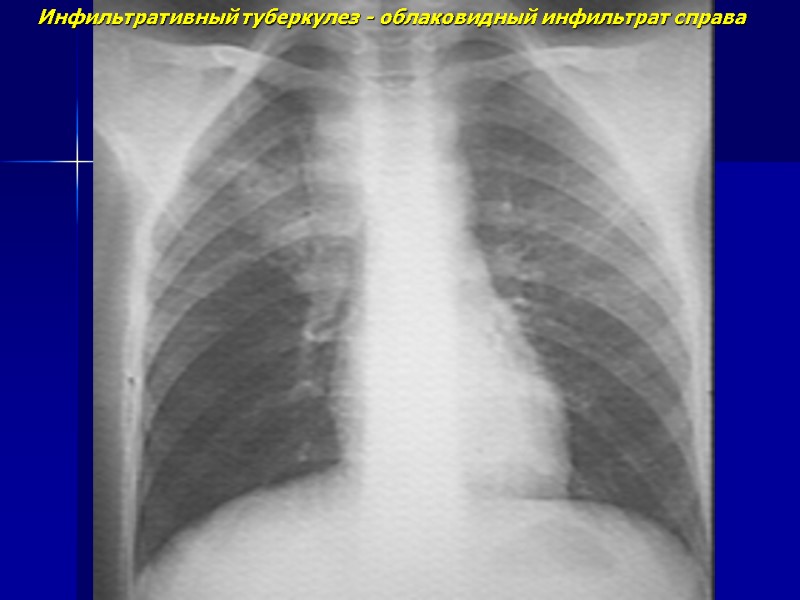

Инфильтративный туберкулез - облаковидный инфильтрат справа

Процесс захватывает более сегмента